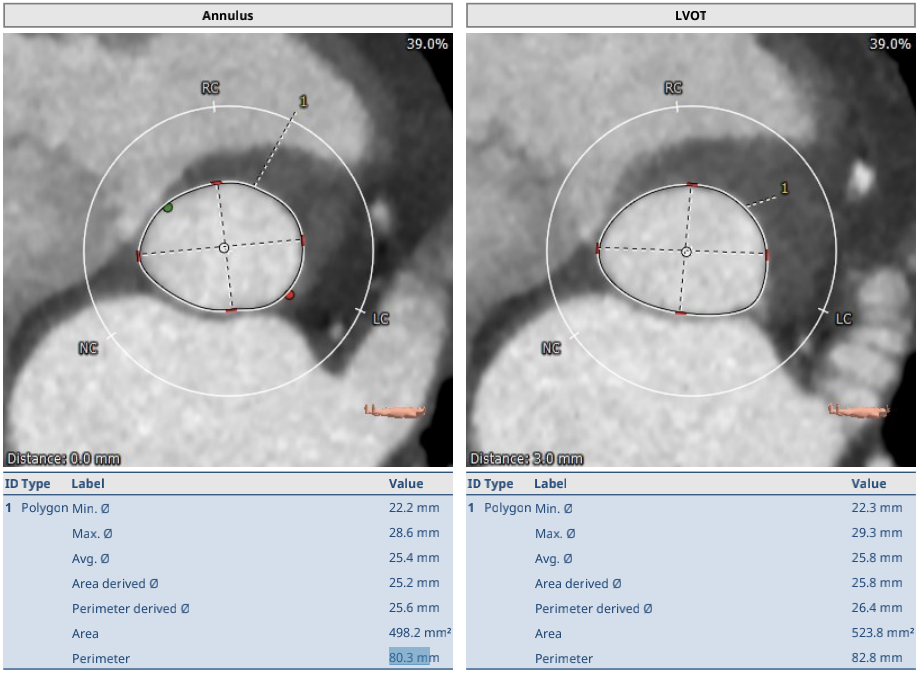

术前CT结果显示,主动脉瓣口面积498.2mm²,瓣环平均直径25.4mm,瓣环周长80.43mm;LVOT面积523.8 mm²,LVOT平均直径25.8mm;升主动脉平均直径29.2 mm;心夹角44°;左冠开口高度15.5mm、右冠开口高度17.3mm。